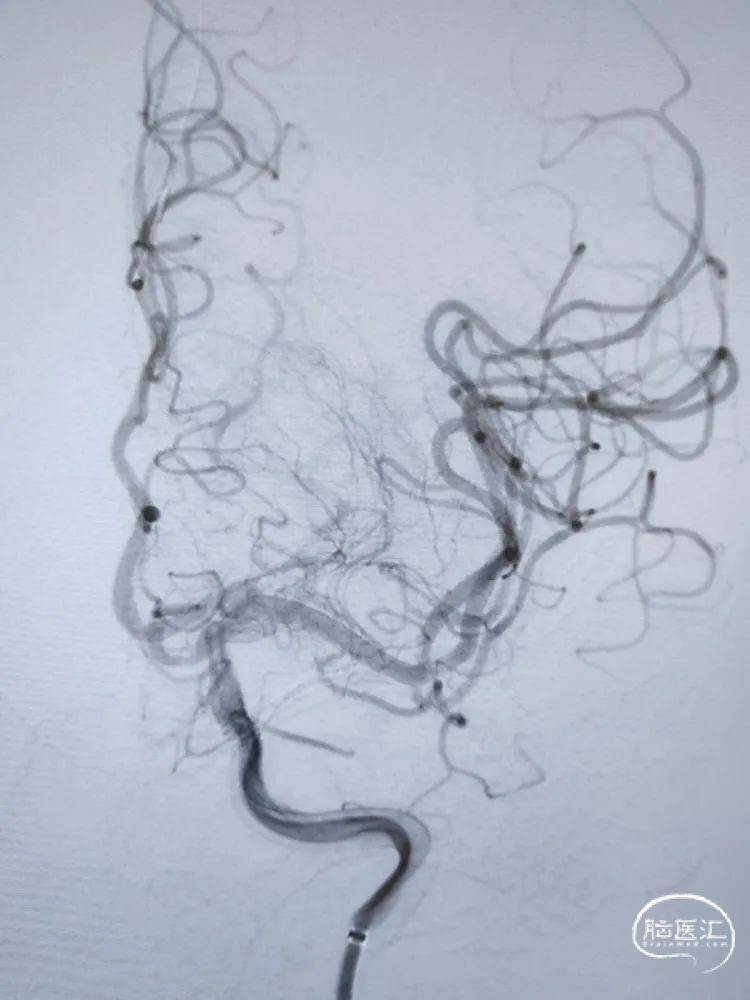

留置微导丝,撤出支架释放系统,观察10分钟后造影提示血流无异常,遂撤出微导丝。侧位、正位造影减影像和非减影像提示颈内动脉海绵窦段支架内和远端血流通畅,支架顺应血管贴壁良好;由于近端血流改善,后交通动脉充分显影。